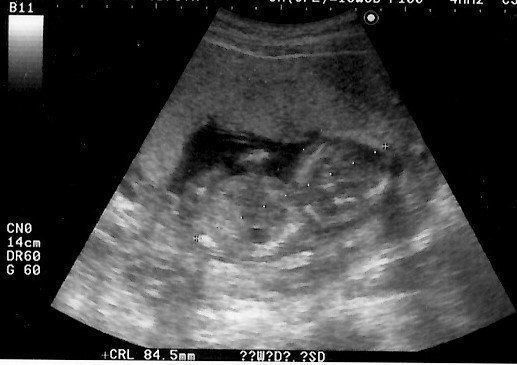

妊娠9週目のエコー写真 胎児の姿が見えてきた!

エコー画像で頭と胴体が分かれた人間らしい姿を見て、いよいよ妊娠したという実感がわいてきました。それと同時に、このまま無事に育ってくれるのだろうかという不安で毎日祈るような気持ちでいました。いまだにこの画像を見るたびに、この時の不安でたまらなかった自分の気持ち、そして生命の神秘を目の当たりにしたときの厳粛な気持ちを思い出し、胸がいっぱいになります。